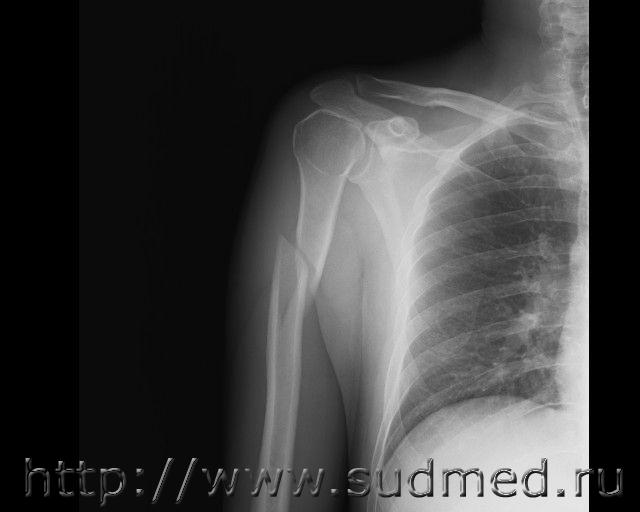

Судебная медицина - Прикрепленное изображение

Снимок сделан не корректно. По правилам рентгенологии обязательно должно быть видно 2 сустава (плечевой и локтевой).

Деформация кручения, иного не дано. Но вот в какую сторону кручение - внутрь (по версии потерпевшего) или наружу - не понятно по р-грамме в одной проекции. Нужен боковой снимок.

Обычно винтообразные косые образуются при падении на выпрямленную руку с упором на основание ладони.

Этого снимка, на мой взгляд, достаточно для вывода о механизме образования перелома.

Этот перелом образовался от действия ротационной (скручивающей) силы на диафиз плечевой кости. Его формирование возможно как при при падении на выпрямленную руку с упором на основание ладони (или на локоть) либо при выкручивании руки. Этот перелом не мог сформироваться при падении с ударом областью, в которой образовался перелом.

Экспертиза проведена правильно. Её выводы обоснованы. На экспертизу были представлены две версии: 1.падение, при этом рука была выпрямлена, располагалась под туловищем, верхняя часть плеча касалась края ребра лестничной ступени. При падении таким образом такой перелом получить категорически невозможно. Так можно сломать плечевую кость, но перелом будет иметь совершенно другой вид (может образоваться поперечный, косо-поперечный, оскольчатый перелом, но не винтобразный).

2."загиб руки" (с вполне возможным элементом ротации). Не исключается возможность причинения винтообразного перелома при таких обстоятельствах.